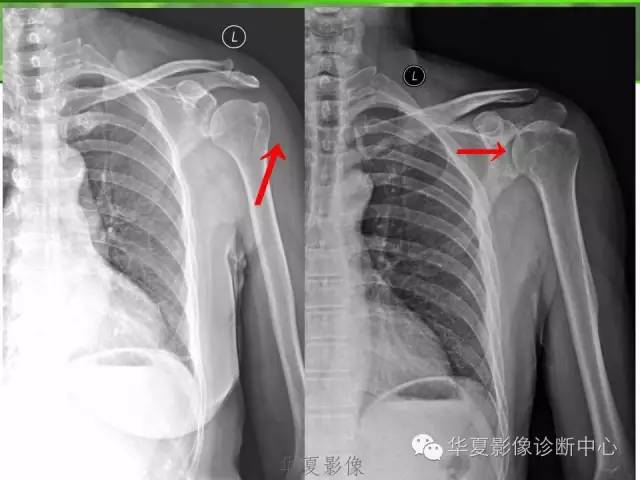

(1)早期的特征性改变主要是显示肩峰下脂肪线模糊变形乃至消失。所谓肩峰下脂肪线是指三角肌下筋膜上的一薄层脂肪组织在X线片上的线状投影。当肩关节过度内旋位时,该脂肪组织恰好处于切线位,而显示线状。肩周炎早期,当肩部软组织充血水肿时,X线片上软组织对比度下降,肩峰下脂肪线模糊变形乃至消失。

(2)中晚期,肩部软组织钙化,X线片可见关节囊、滑液囊、冈上肌腱、肱二头肌长头腱等处有密度淡而不均的钙化斑影。在病程晚期,X线片可见钙化影致密锐利,部分病例可见大结节骨质增生和骨赘形成等。此外,在肩锁关节可见骨质疏松、关节端增生或形成骨赘或关节间隙变窄等。